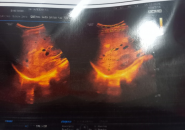

Hình Ảnh Siêu Âm Gan Có Nốt Âm, Có Phải Nang Sán Không?

Chào Bác sĩ, em năm nay 40 tuổi, em bị ngứa da mãn tính kéo dài gần năm năm nay không khỏi, da có lúc sạm và vàng da, đôi lúc đau mạn sườn phải, người thấy mệt...